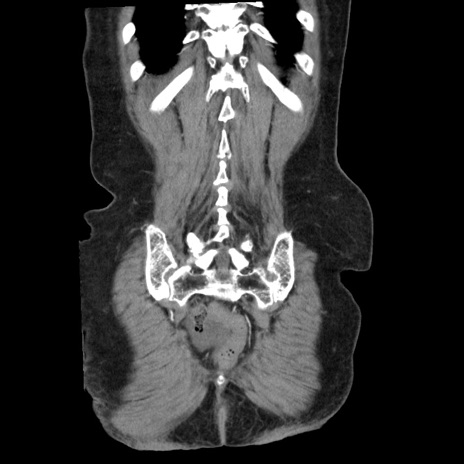

矢状断像

【症例】80歳代女性

【主訴】腹痛

【現病歴】8時間前から腹痛あり来院。

【既往歴】糖尿病、脂質異常症、子宮体癌にて子宮全摘術

【身体所見】意識清明・会話良好だが腹痛で苦悶様、全腹部にわたって反跳痛と圧痛あり

【データ】WBC 13600、CRP 0.14、LDH 224、CK 90